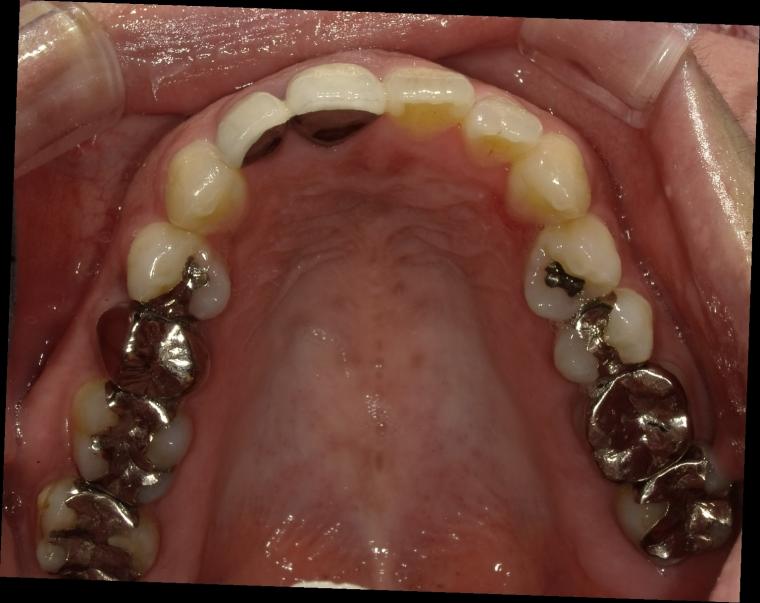

BEFORE

53歳女性/上1本欠損/インプラント埋込手術

前歯の詰め物が割れたかもしれないの主訴でご来院された方です。

保存状態が厳しかった為、上顎側切歯の抜歯となりました。

抜歯後に土台となる骨を作る処置の後、インプラントを1本埋入しました。